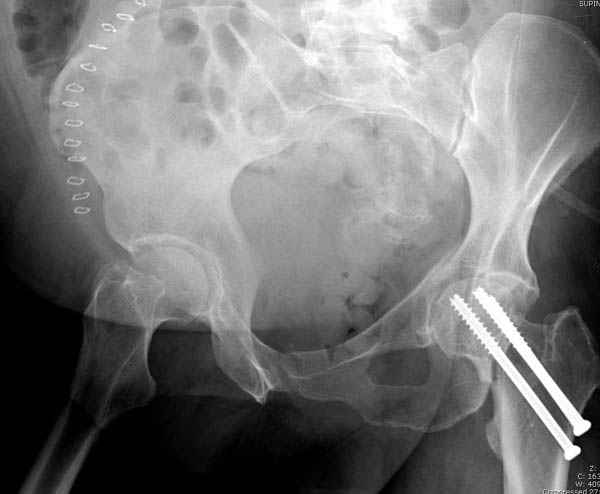

Долгое ожидание повышает риск АВН головки,

рекомендуется ургентная фиксация шейки в первые сутки, а в дальнейшем таз.

В данный момент скелетное вытяжение получается через перелом шейки, а

фиксированный перелом шейки будет участвовать в процессе вытяжения через

канюлированные  шурупы.

Перелом шейки смогли зафиксировать через пару дней, ацетабулум до сих

пор не оперирован, на вытяжении.

Из-за упущенного времени (три недели с момента

поступления) ацетабулум ведем консервативно.

На снимке ацетабулума редко встречающийся очень низкий перелом,

наверное, трудно было репозицию через один доступ? Перелом как бы

замкнулся в квадрилатеральной поврехности.